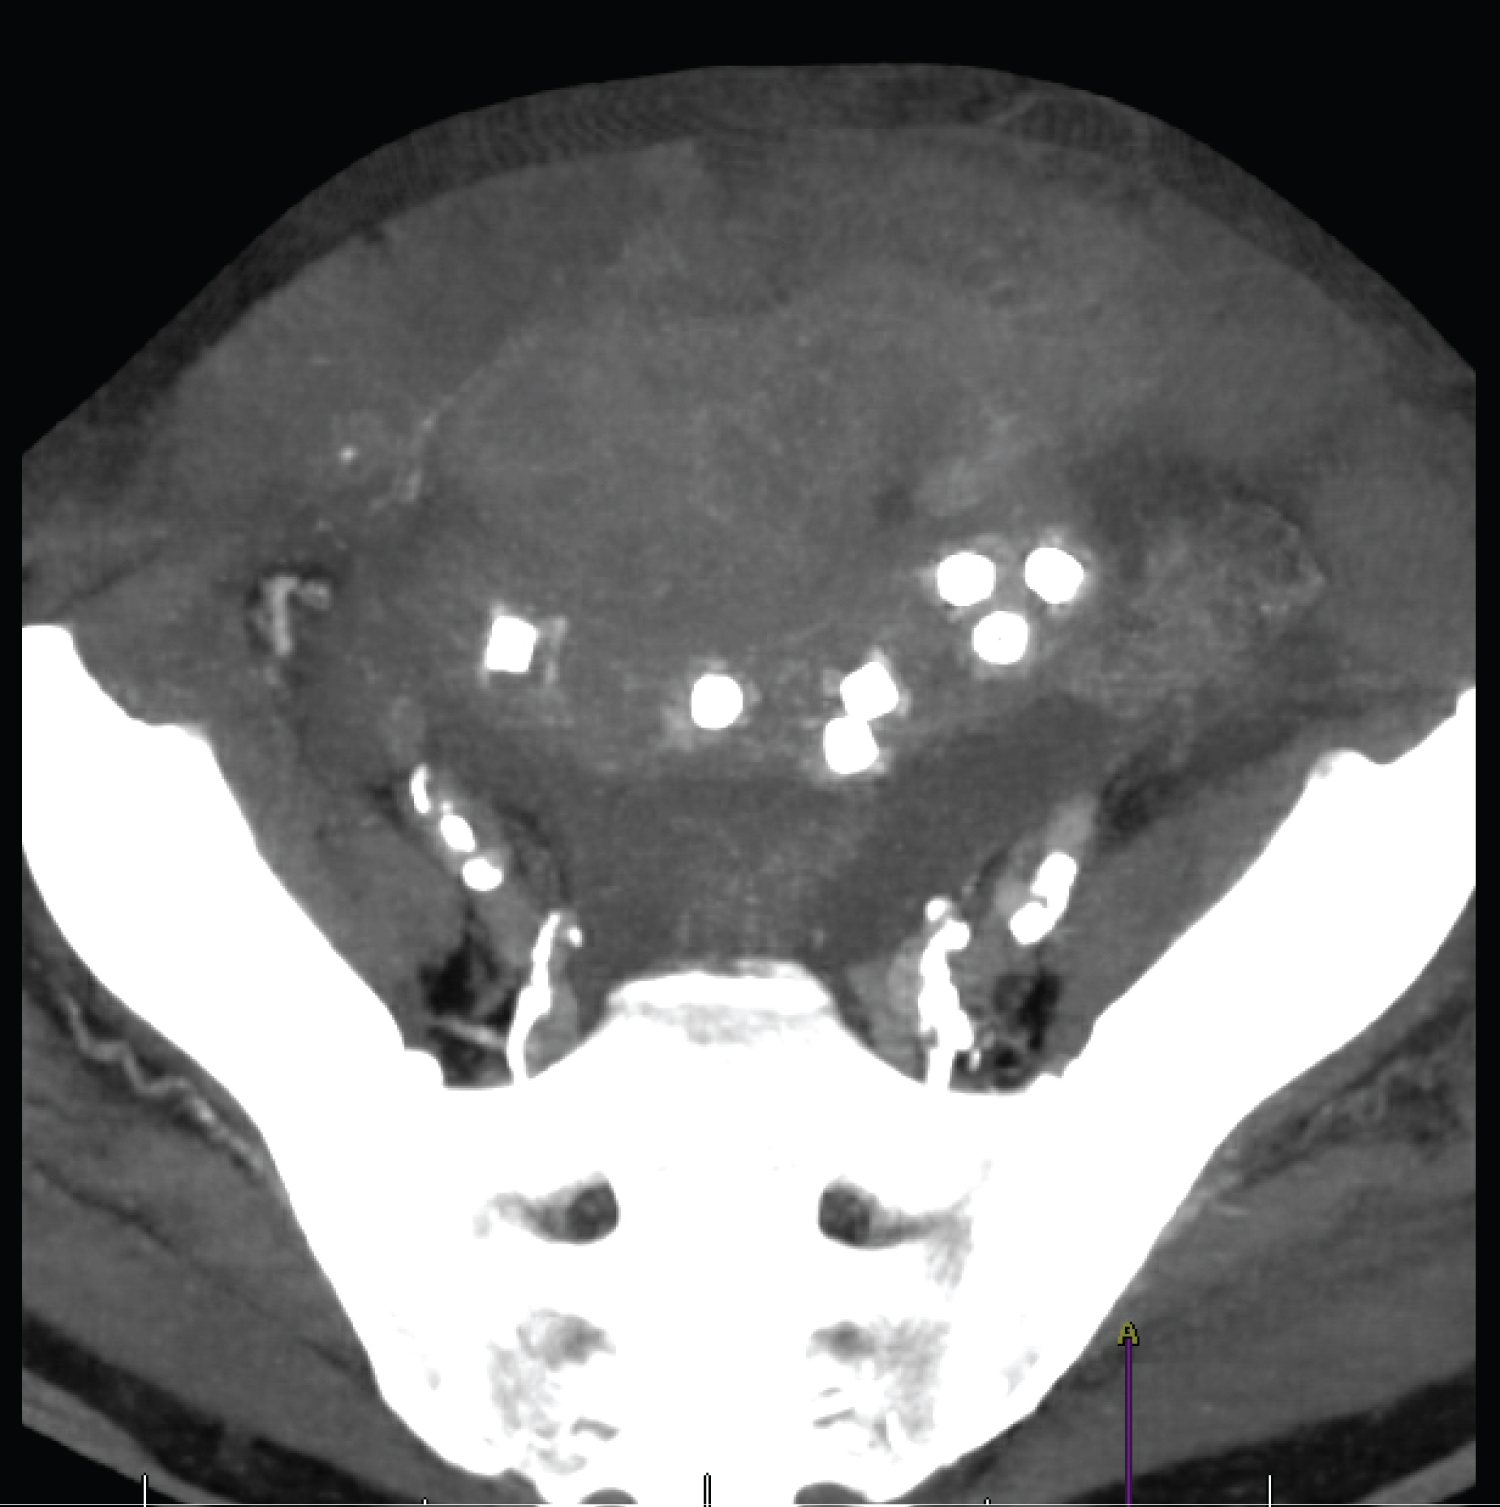

In February 2021, the patient was referred to our emergency department due to abdominal pain, abdominal distension and total constipation throughout a 72 hours' period. He presented with nausea and vomiting through the tracheostomy. He did not refer swallowing his voice prosthesis and had an unremarkable digestive history. He was dyspnoeic (respiratory rate 23/min) with 92% of saturation, had tachycardia (100/min), normal blood pressure (135/90) but was afebrile. The abdomen was painful on palpation with tenderness in four quadrants. Laboratory work-up indicated an inflammatory syndrome with CRP of 428 mg/L and leucocytosis of 12.9 G/L. The blood gas showed acidemia with hyperlactatemia (3.2 mmol/l). A CT-angiography of abdomen revealed a pneumoperitoneum in the right iliac fossa associated with intra-abdominal free fluid. The walls of the distal ileum were globally thickened (Figure 1). Remarkably, 7 tubular foreign bodies were discovered inside the ileum.

Figure 1: Thickness of the walls of the distal ileum. View Figure 1